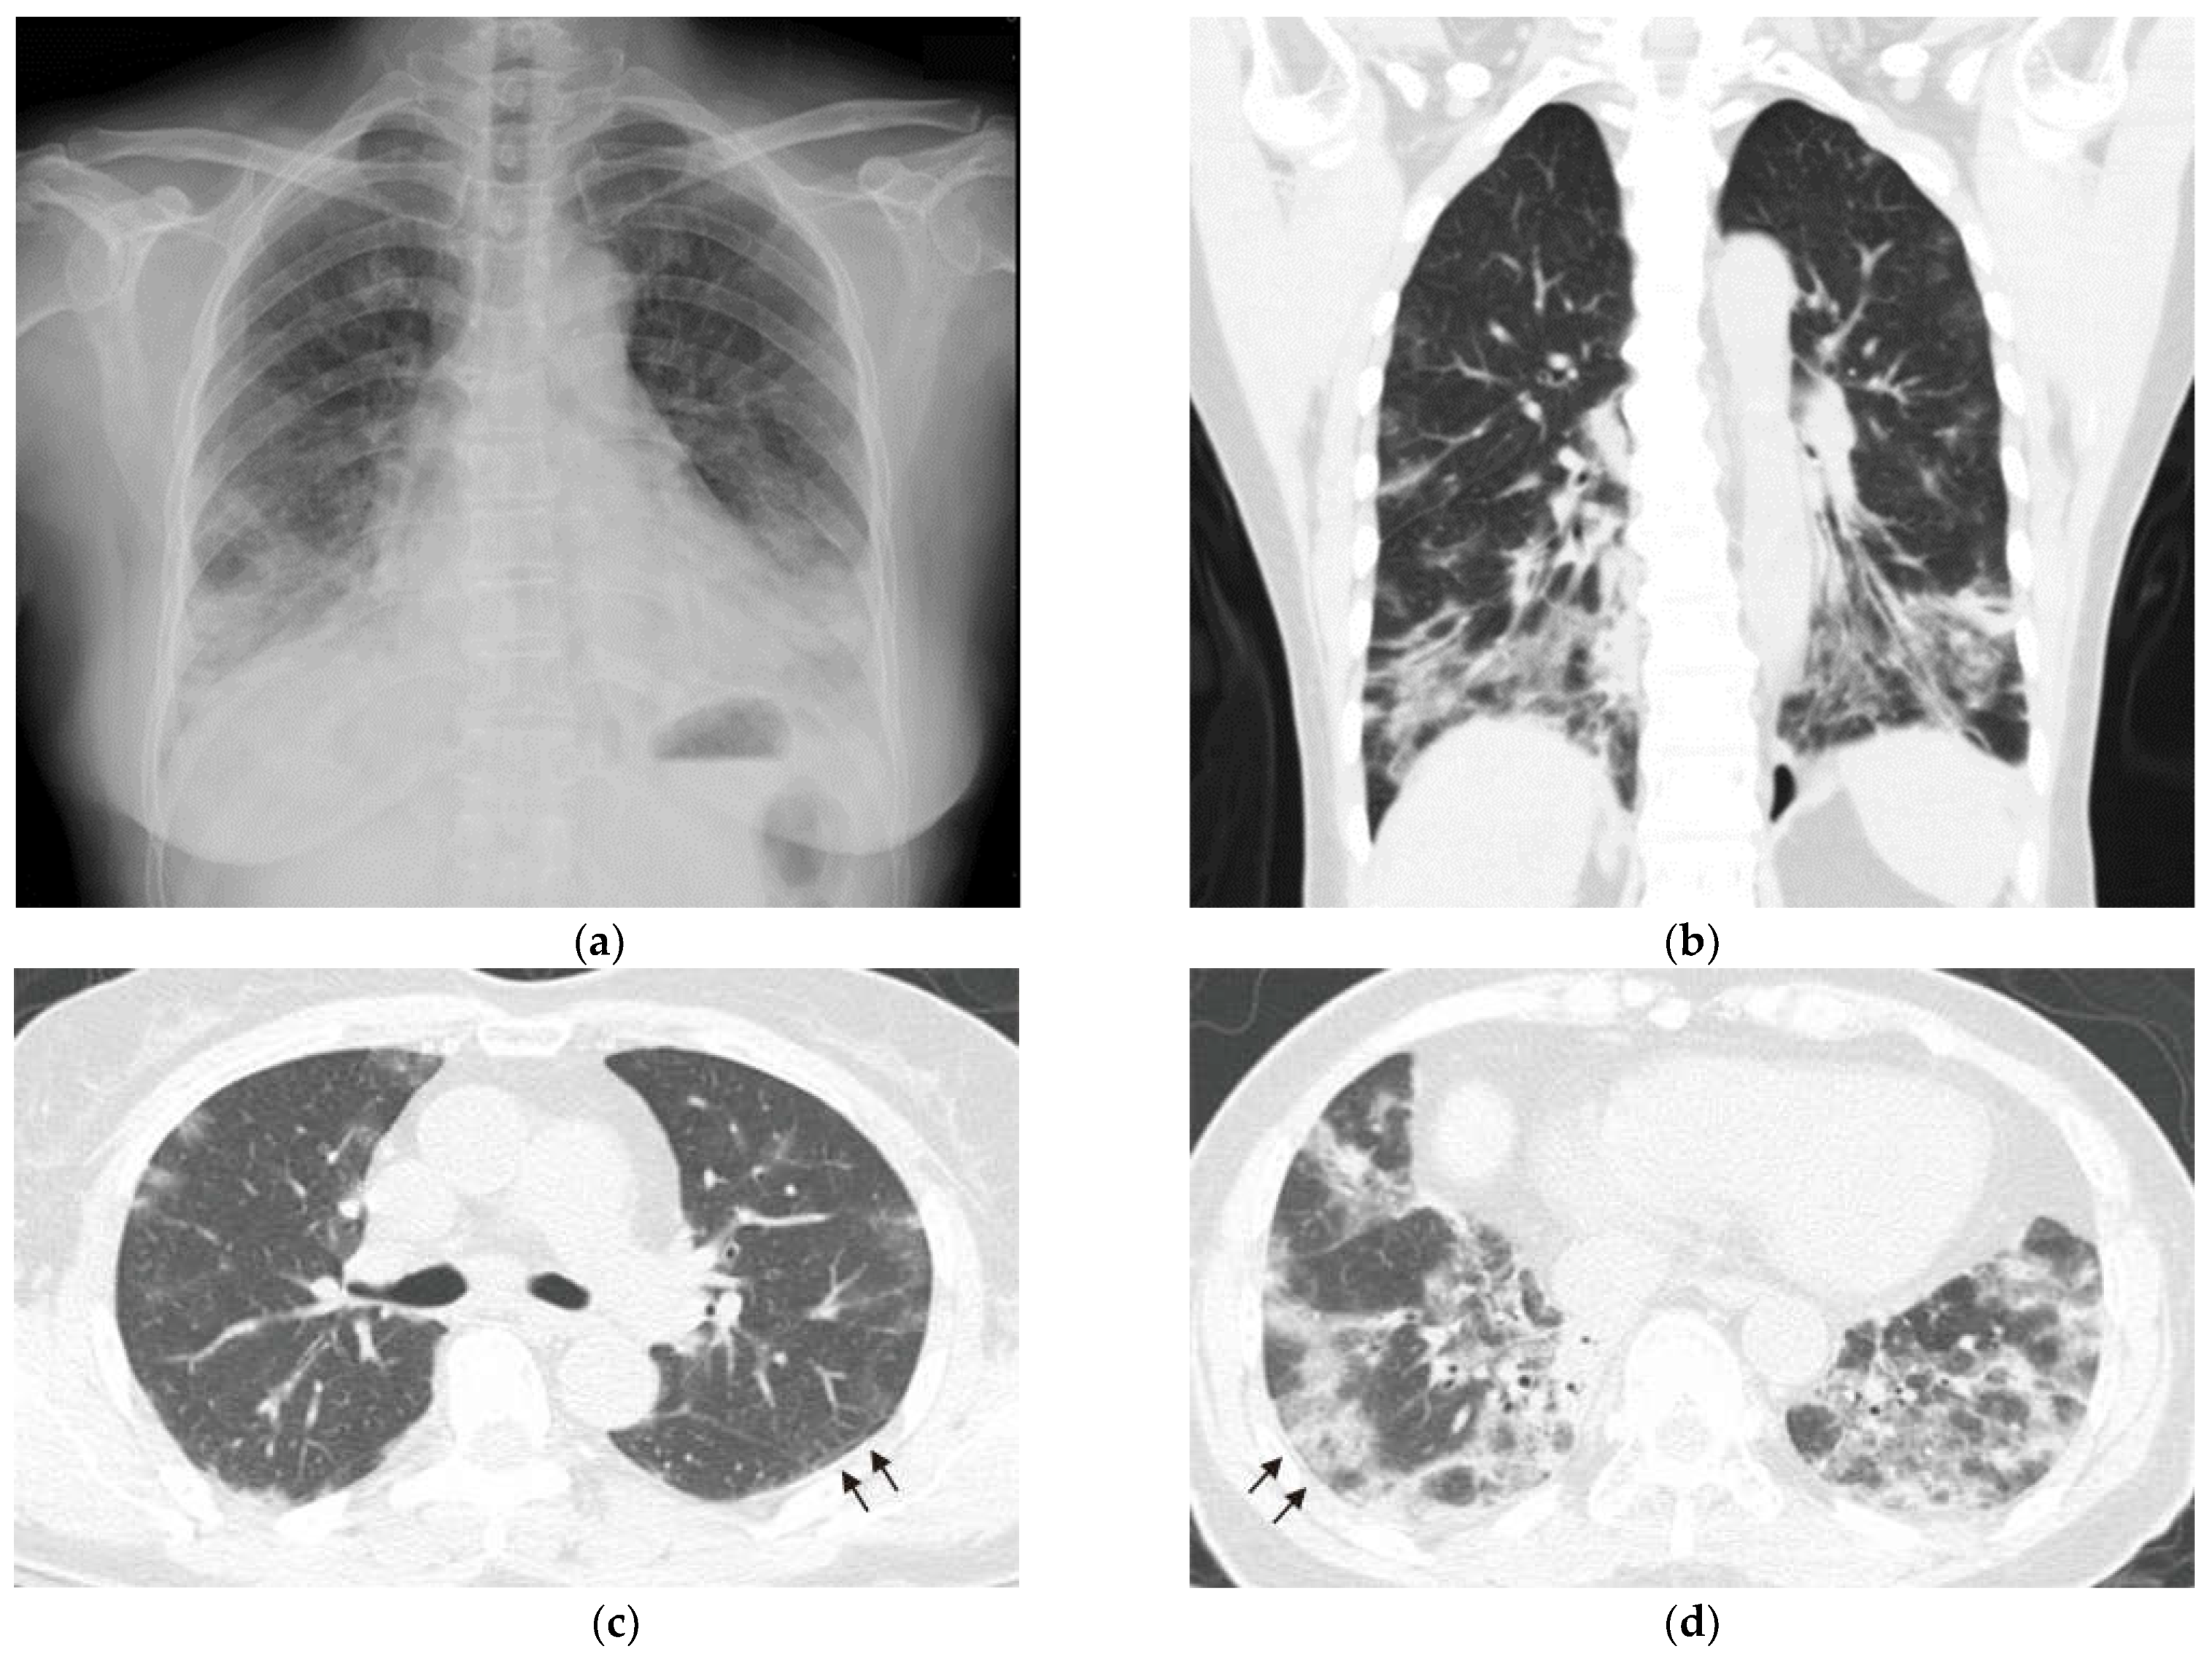

Two days before admission, she presented at our emergency department with fever, cough, and progressive dyspnea. An examination revealed that she had tachypnea and an oxygen saturation of 66% while breathing ambient air. She received oxygen therapy through a non-rebreathing mask. Her white-cell count was 12,800 per µL (reference: 4140–10,520 per µL), and her C-reactive protein was 59 mg/L (reference: <5 mg/L). Her hemoglobin, platelet, serum procalcitonin, B-type natriuretic peptide, creatine kinase, liver, and renal functions were all normal. Detailed serologic testing disclosed a positive anti-Jo-1 of 89 EliAU/mL (reference: <7 EliAU/mL) and anti-Ro52 of 3+ (reference: negative). Her rheumatoid arthritis factor, anti-La, anti-SCL-70, anti-ds DNA, anti-MDA-5, and other myositis-specific autoantibodies (MSAs) were all negative. A chest radiograph revealed consolidations in the bilateral lower lungs (Figure 2a).

After the patient was admitted to an intensive care unit, we shifted oxygen supplementation to a high-flow nasal cannula that delivered a fraction of inspired oxygen (FiO2) of 80%. Chest CT revealed consolidations and ground-glass opacities over the bilateral lungs with peripheral and lower lung zone predominance (Figure 2b–d). Sputum cultures showed no growth of bacteria, fungus or mycobacteria. Given the features of positive anti-Jo-1 and anti-Ro52, the absence of extrathoracic manifestations, and the failure to meet specific CTD criteria, a diagnosis of IPAF was made after a multidisciplinary discussion involving two pulmonologists, a rheumatologist, and a radiologist. Other diagnoses, including bacterial pneumonia, adult respiratory distress syndrome, cardiogenic pulmonary edema, and cryptogenic organizing pneumonia were further excluded based on her clinical presentations and laboratory data. Additionally, her clinical features were unable to fulfill the diagnosis of anti-synthetase syndrome based on the criteria proposed by Solomon et al. [4]. The patient received methylprednisolone pulse therapy (500 mg/day for 3 days), followed by one dose of 500 mg cyclophosphamide. On the 5th day of hospitalization, she was intubated for severe hypoxemia. She also received treatment with prone positioning and broad-spectrum antibiotic piperacillin/tazobactam (4.5 g every 8 h), and her oxygen saturation improved gradually. On the 16th day of hospitalization, she was extubated successfully and discharged on the 26th day.

Figure 2. Chest imaging upon admission to the intensive care unit (a) Chest radiograph revealed new development of bibasilar consolidations. (bd) Computed tomography scans revealed consolidations and increased ground-glass opacities over the bilateral lungs.